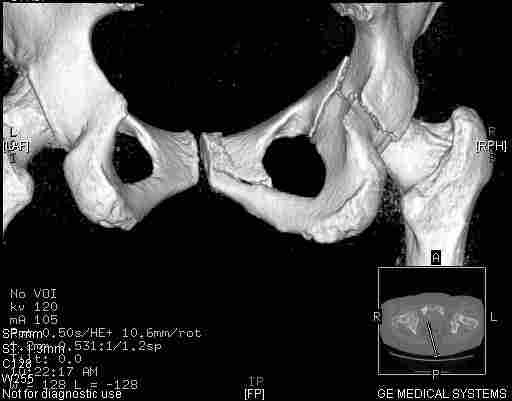

Удалось сегодня вывести пациентку в соседнюю больницу, где есть кт. Срезы сделаны только горизонтальные.

Следом 3d

Приветствую,Антон.Рункова рядом нет,но после полученных данных КТ,обсуждали совместно.Итог обсуждения-развернутый ответ дать не получится,т.к.срезы выбраны не информативные.Если ориентироваться на данные 3D,то ,ИМХО,можно лечить на вытяжении.